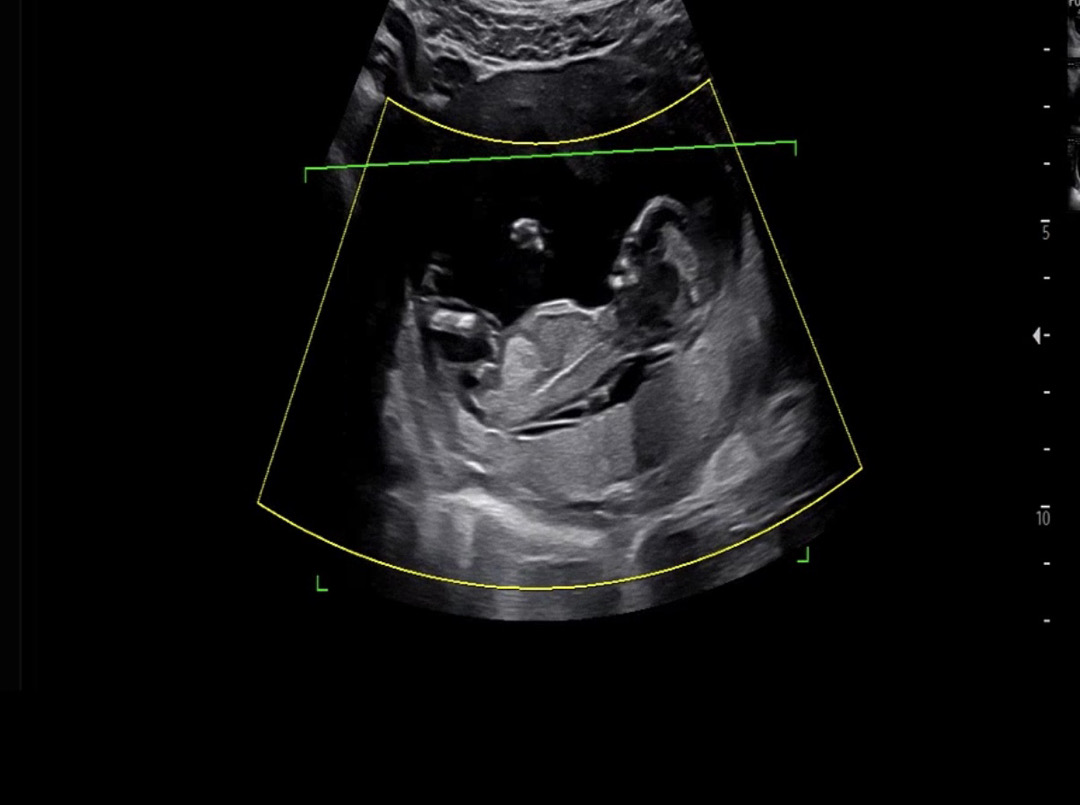

각도법 잘 보시는 맘분들 딸일까요 아들일까요 ?! 12주차 촘파사진이예요 !